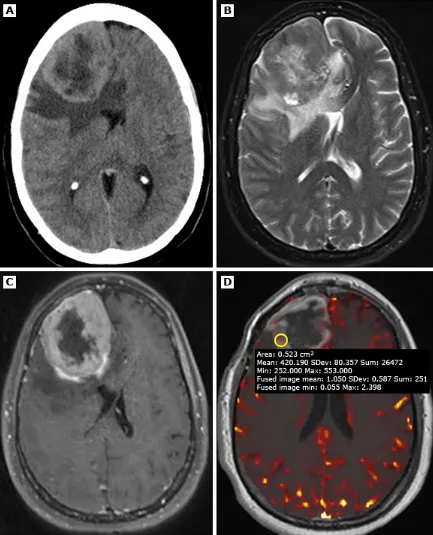

仅根据神经影像学来鉴别非典型或恶性脑膜瘤与良性脑膜瘤较为困难。下列MRI特征可能提示存在高级别脑膜瘤而非良性脑膜瘤:

●肿瘤边缘无等密度脑嵴液包绕,或明显侵入脑实质

●肿瘤内囊性或坏死性改变

●肿瘤扩展穿过颅底

●表观弥散系数(apparent diffusion coefficient,ADC)低

●灌注加权MRI显示脑血容量升高

一名49岁患者,经病理证实为3级(间变性)脑膜瘤。A(平扫头颅CT):显示右侧额叶巨大占位性病变,密度不均,周围伴血管源性水肿,并导致明显占位效应。B(横轴位T2加权MRI):肿块呈不均匀信号强度,周边可见相对于高信号核心的厚壁低信号环。C(增强后MRI):强化肿块内部可见中央强化减低区,提示存在中央坏死。D(灌注加权MRI):相对脑血容量(rCBV)未见升高。

但上述表现的敏感性、特异性都不够高。此外,如条件允许,大多数脑(嵴)膜瘤的初始治疗方法都为手术切除,具体取决于病灶的大小和部位,以及患者的总体情况和症状。